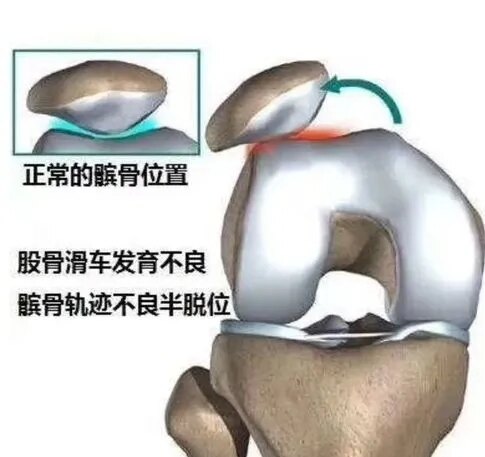

髌骨和股骨滑车是天衣无缝的匹配的,正常的髌骨,在滑车上,不偏内也不偏外。可人的生长发育那可能都那么完美呢?人们都是或多或少的存在些发育上不足。对于髌骨,时常偏外,就是常见的髌骨半脱位类型。

那么偏外,会出现什么问题呢?最典型的,就是上下楼疼痛,下蹲困难。严重的平底走路都费劲。主要是,匹配不好,局部压强大,磨损所致。